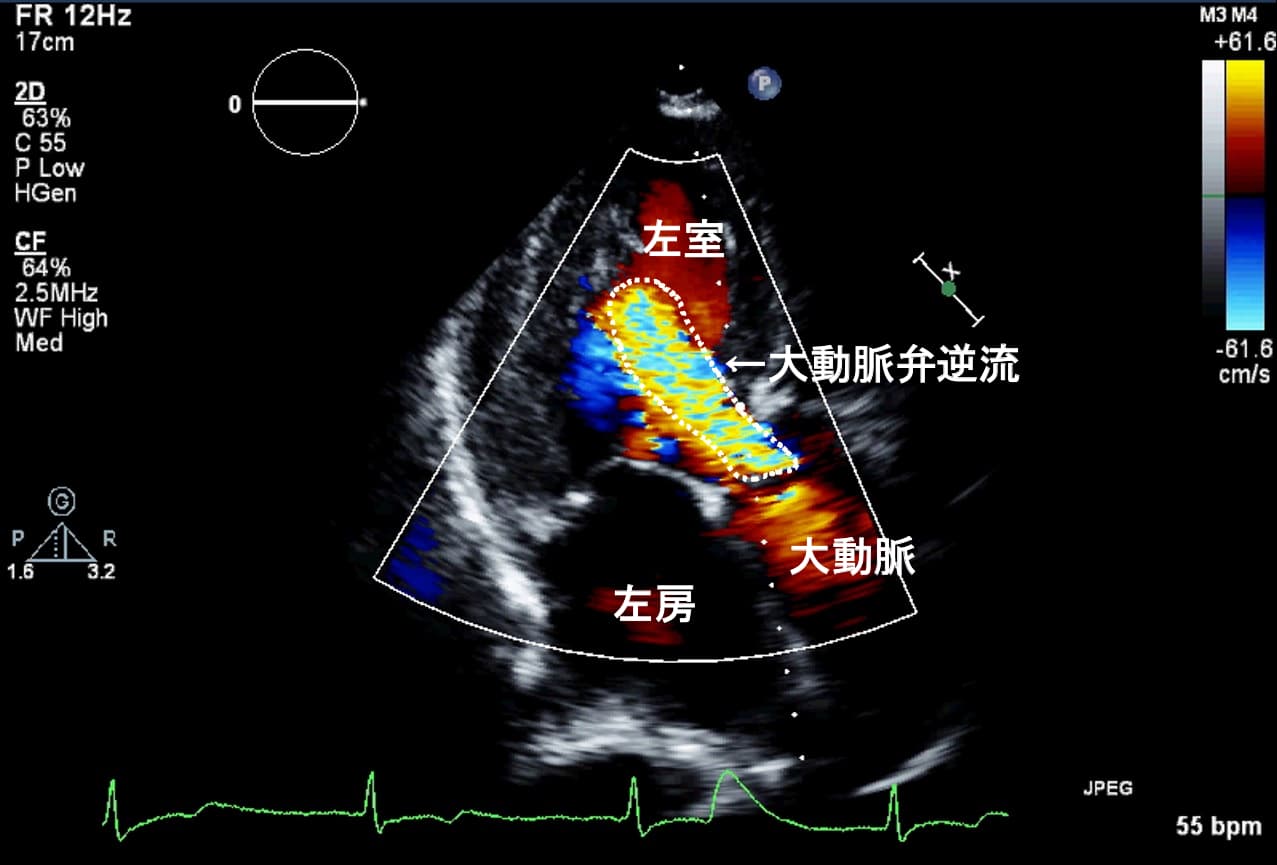

次に、あなたは横向きに寝て、医師があなたの心臓の安静時の心エコー図または超音波検査を行います。特殊なジェルを皮膚に塗布し、トランスデューサーと呼ばれる装置を使用します。

この装置は音波を発し、心臓の動きや内部構造の画像を作成します。